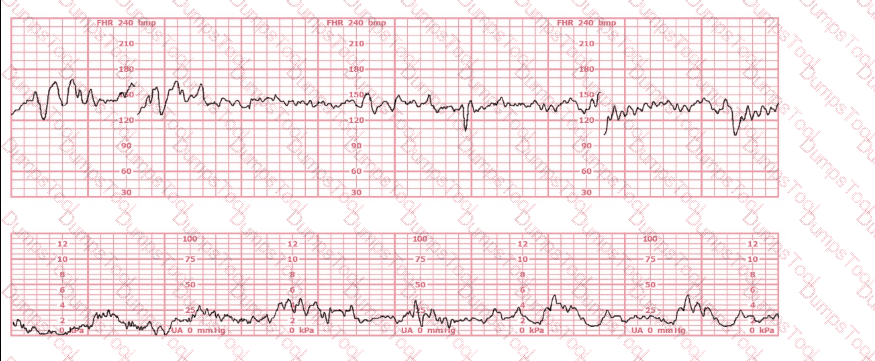

A nulliparous woman at term presents with leaking fluid. Rupture of membranes confirmed. After 6 hours she is completely dilated, +2 station, has been pushing 2 hours with oxytocin at 10 mU/min. The fetal tracing is shown. What is the next step in management?

This fetal heart rate tracing is from a woman in the second stage of labor. This tracing is best interpreted as: